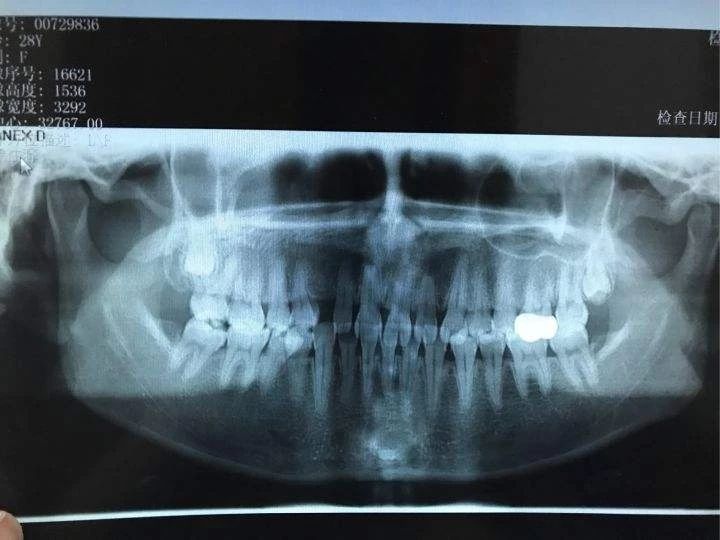

步骤一:拍片

主要指的是拍牙齿X光片和头部侧位片,利用X光将牙齿的形态拍出来,再拍出头部骨骼的光片,目的是为了看牙齿和骨骼的发展方向,然后正畸医师通过拍片情况制定准确的矫治方案。